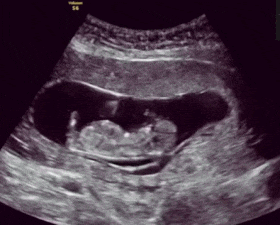

原因很简单 , 你是靠一日三餐获取营养 , 可胎宝宝不是 , 他是“吸血” , 哦不 , 是通过胎盘和脐带从血液中吸收营养的 。

也就是说妈妈吃进去的东西 , 并不能直接输送给胎儿 , 而是要转化成营养储存在体内 。

换句话说 , 只要你身体倍儿棒、不缺营养 , 胎宝宝就根本不会饿 , 毕竟地主家有余粮 。 即便你饿上一顿两顿 , 也不影响他吃香喝辣 , 天天打饱嗝 , 没事儿就蹦跶 。